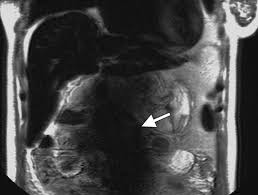

How will you get the test results? The mri of the abdomen will take approximately 60 minutes. What does the procedure involve? In some cases, it may take up to about 2 hours. Abdominal mris are used for a variety of reasons, such as examining:

What do i do after my scan? Newer scanners complete the process in less time. But the magnet is very powerful. In some cases, it may take up to about 2 hours. Do you have to drink anything before a mri scan? Most pelvis mri exams are done in the main hospital, acc or placer clinics. The mri of the abdomen will take approximately 60 minutes. How long to wait after mri? Abdominal mris are used for a variety of reasons, such as examining: How will you get the test results? Please contact the doctor who ordered the test for any test results. What are the risks of an mri of the abdomen? How to prepare for the test:

How long to wait after mri? How long does it take to get mri scan results? Most pelvis mri exams are done in the main hospital, acc or placer clinics. What are the risks of an mri of the abdomen? The mri of the abdomen will take approximately 60 minutes. What does the procedure involve? In some cases, it may take up to about 2 hours. Jul 08, 2017 · preliminary results from an abdominal mri may come within a few days, but comprehensive results can take a week or more.

The doctor who ordered the test will receive the results. Do you have to drink anything before a mri scan? Abdominal mris are used for a variety of reasons, such as examining: May 15, 2021 · an abdominal mri generally takes about 30 to 90 minutes. Most pelvis mri exams are done in the main hospital, acc or placer clinics. There are no known harmful effects from the strong magnetic field used for an mri. Newer scanners complete the process in less time. Please contact the doctor who ordered the test for any test results. The test usually takes 30 to 60 minutes but can take as long as 2 hours. How long until mri scan results come back? Jul 08, 2017 · preliminary results from an abdominal mri may come within a few days, but comprehensive results can take a week or more. What does the procedure involve? How to prepare for the test: